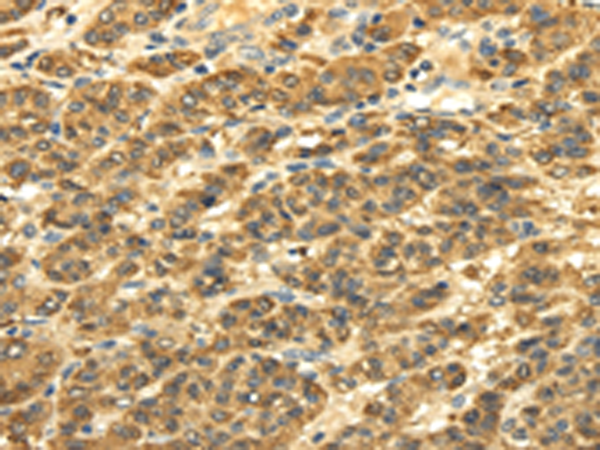

分类: 科研抗体货号: P12199别名: CRT; CT1; CRTR; CTR5; CCDS1应用: IHC反应种属: Human, Mouse, Rat